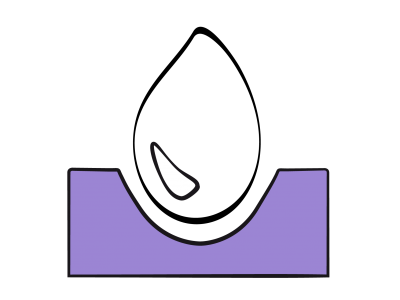

La dysfonction diastolique et la baisse de compliance conduisent à une augmentation des pressions pour le même volume de remplissage et rendent le débit cardiaque davantage dépendant de la précharge, car le ventricule fonctionne sur une courbe de Starling très redressée (Figure 23.5).

Figure 23.5: Relations pression/volume du VG en systole (A) et en diastole (B). A: Courbes de Frank-Starling du VG illustrant la relation entre la précharge et la performance systolique. Courbe normale (en vert), courbe en cas de dysfonction systolique (en rouge), et en cas de dysfonction diastolique (en violet). La courbe de Starling du VD (en pointillé) est très plate, ce qui signifie que le débit du VD normal ne dépend que très peu de la précharge. B : Courbe de compliance normale du VG (en bleu) et lors de dysfonction diastolique (en rouge). Dans ce deuxième cas, une pression de remplissage normale (P) correspond un volume ventriculaire plus petit (V’) que la norme (V) en cas de dysfonction diastolique; le sujet peut être hypovolémique avec une POG (PAPO) normale. La normovolémie d’un sujet souffrant de dysfonction diastolique (V’’ rouge) est une pression de remplissage (P’) qui correspond à une hypervolémie (V’’ bleu) chez un sujet normal.